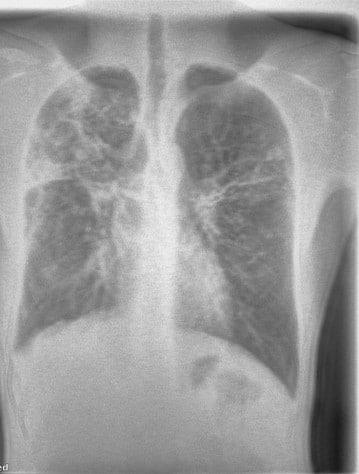

Unlike symptom screening, imaging can reveal structural changes in the lungs, even in patients who do not report symptoms.

“Even those that are asymptomatic, you can begin to see features on the lung image that suggest TB.”

A 22-year-old male presented with a one-month history of dry cough and chest pain. Chest X-ray findings were suggestive of tuberculosis, later confirmed by GeneXpert testing.